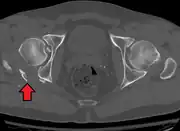

Axial CT image (viewed on bone windows) of a complex comminuted left acetabular fracture involving both anterior and posterior columns.